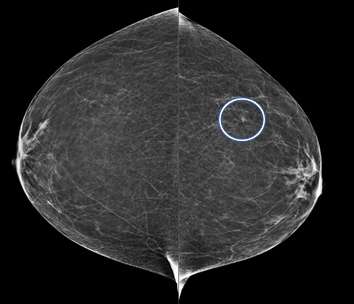

Developing Asymmetry:

A developing asymmetry is an asymmetry that is larger or more conspicuous compared to prior exams3. Since breast tissue tends to become less dense with age, developing asymmetries are usually more concerning and may warrant additional workup such as biopsies.

Serial MLO view of the left breast (from oldest to newest) demonstrate increase density in the left superior breast consistent with a developing asymmetry. This particular case turned out to be biopsy-proven pseudoangiomatous stromal hyperplasia.